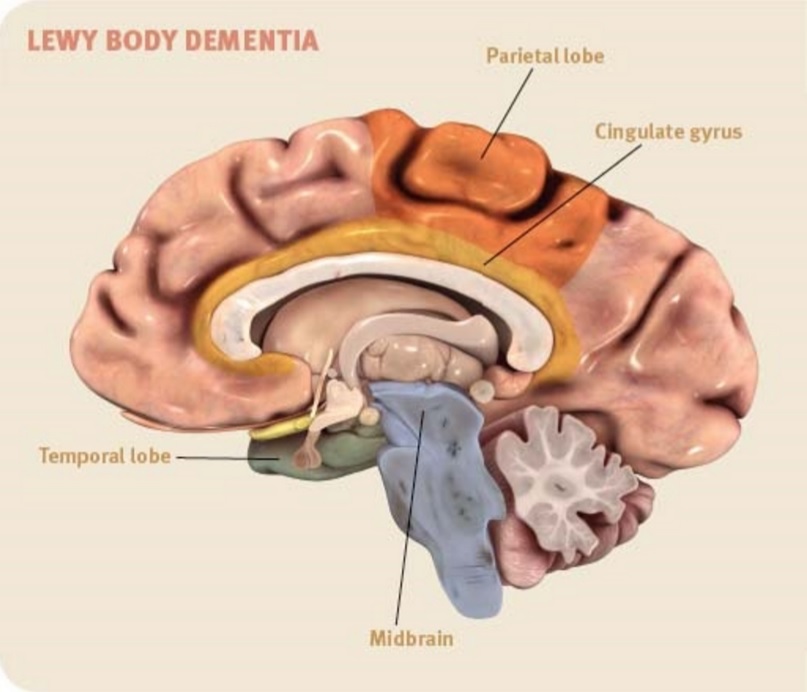

The Neurologist Is In: Lewy Body Dementia Is Often Unknown and Unrecognized

“Lewy Bodies in Dementia and Parkinson’s Disease” Infographic (NIH …

Dementia With Lewy Bodies Illustrations, Royalty-Free Vector Graphics …

What is Lewy Body Dementia?? – The Ruby Pardue Blackburn Adult Day …

Pathological findings of dementia with Lewy bodies on autopsy. (a …